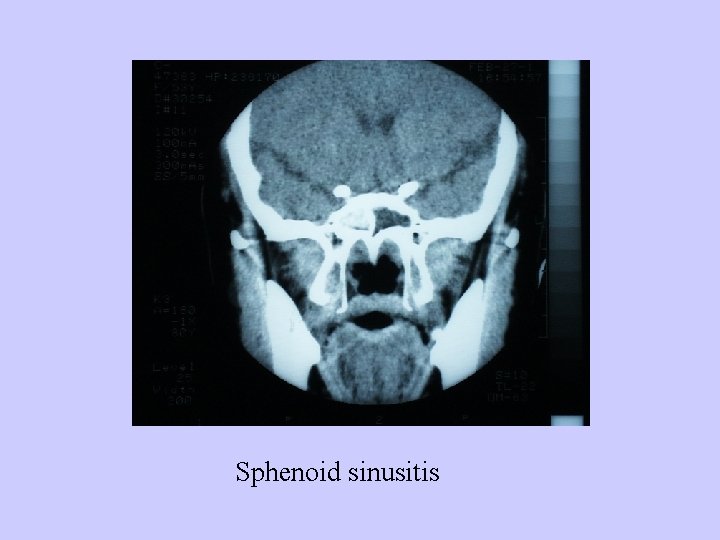

Diagnosis: 1、History; 2、Examination:anterior rhinoscopy, nasal endoscopy 3、Radiological examination:CT or MRI 4、Puncture and irrigation of sinus

Sphenoid sinusitis